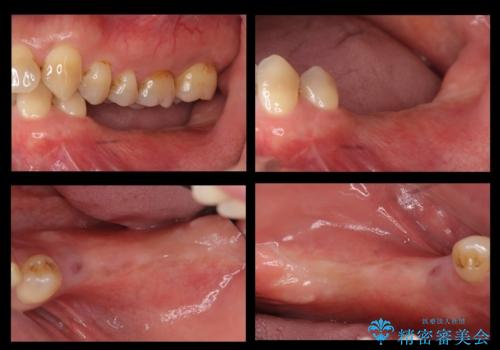

奥歯のインプラント 大人になって残っていた乳歯がダメになった

- 奥歯のブリッジの違和感を主訴に来院。

乳歯を使ってブリッジにしていましたが、支台歯が両方虫歯になっており、根が短くなって持たなくなった乳歯を抜いて、インプラントにすることになりました。

治療スケジュールとしては

①保存不可能な歯の抜歯

②6か月待つ